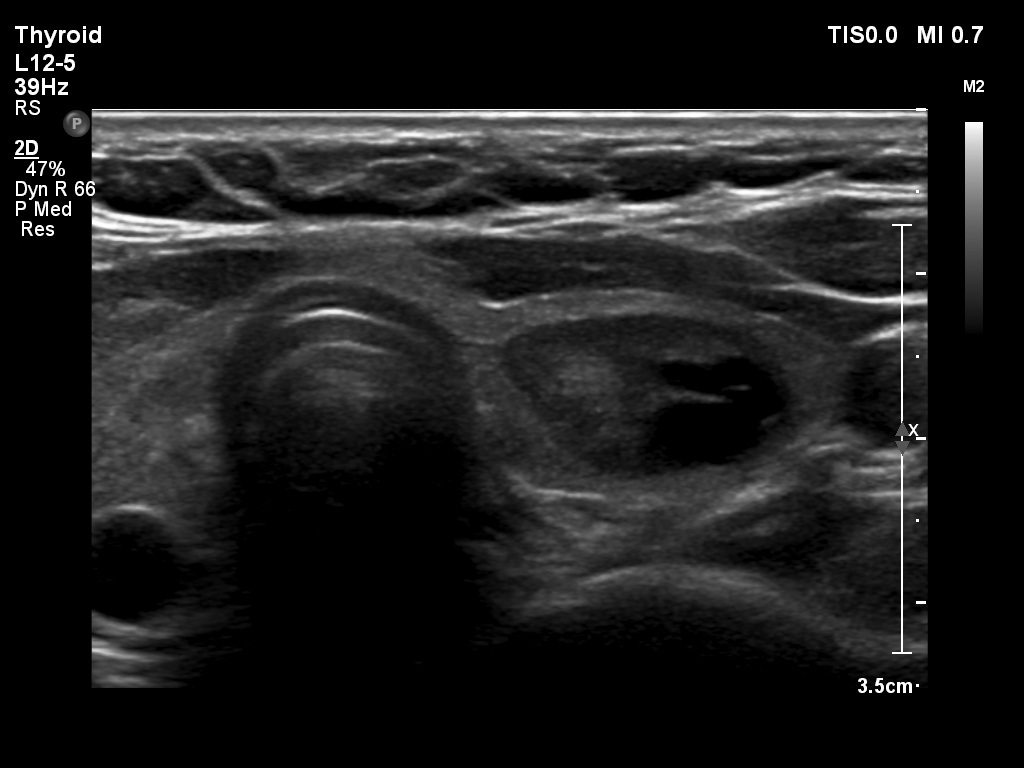

Second examination 2 years later (3rd row of images)

Summary of follow-up: the patient had no complaints.

Functional state: euthyroidism with TSH-level 1.76 mIU/L.

Ultrasonography: the ultrasound presentation of the thyroid was basically unchanged except for the presence of cystic area within the nodule. The vascularization and elastography of the nodule were not specific.

Suggestion: to continue the follow-up with ultrasound and TSH determinations every three years.